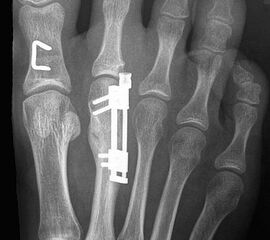

Das im Folgenden vorgestellte Operationsverfahren beschreibt die Kallusdistraktion von Metatarsalia nach den Prinzipien von Ilisarov 21 unter Verwendung eines internen, winkelstabilen Titan-Minifixateur (Klauser 2009). Der interne Distraktor ermöglicht während der Distraktions- und der Durchbauungsphase aufgrund seiner hohen Stabilität je nach Modell (18 mm, 23 mm) eine Verlängerung von bis zu 25 mm. Nach interner Anlage des Minifixateurs, meist lateral, kann über eine kontinuierliche Kallusdistraktion der Metatarsalebogen unter frühzeitiger Mobilisation im Gips oder Short-Walker rekonstruiert werden 15. Über einen interdigital und transcutan ausgeleiteten Aktivatorstab wird die Distraktion vom Patienten selber täglich morgens und abends durchgeführt. Zusätzlich vorliegende Strahlpathologien, wie zum Beispiel eine verkürzte Strecksehne oder ein kontraktes Metatarsophalangealgelenk können im Rahmen der Erstoperation ebenso therapiert werden wie z.B. ein Hallux valgus, ein Hallux valgus interphalangeus und/oder ein Digitus quintus varus (Klauser 2009). Nach Rekonstruktion des Metatarsalebogens wird in einem zweiten, kleinen Eingriff der Aktivatorstab über eine Spezialpinzette diskonnektiert und entfernt, wobei der Distraktor als interne Fixation belassen wird. Die Entfernung des Distraktors erfolgt in der Regel nach 9 – 12 Monaten, da es sich meist um angeborene kindliche Fehlbildungen handelt (Brachymetatarsie) und eine operative Intervention frühzeitig im Kindesalter erfolgen sollte (Klauser 2009).

Meist kam ein 18mm Minifixateur zur Anwendung und ausnahmslos wurde er lateral am Metatarsale implantiert. Bis auf das Metatarsale 5 wurden vom Autor alle weiteren Metatarsalia (MT1 – MT4) isoliert oder kombiniert verlängert. In 7 Fällen wurde eine simultane Verlängerung zweier Metatarsalia (2x MT1 und MT4, 4x MT3 und MT4, 1x MT2 und MT3) vorgenommen. Bei einem Großteil der Patienten musste eine Strecksehnenverlängerung entweder im Rahmen der Erstoperation oder im Rahmen der Aktivatorentkopplung vorgenommen werden. In neun Fällen (ausnahmslos bei Erwachsenen > 30 Jahre) sogar 2x sowohl während des Erst- als auch Zweiteingriffes. Annähernd regelhaft sind bei den eben genannten Eingriffen Arthrolysen des Metatarsophalangealgelenks des betroffenen Zehenstrahls erforderlich, da durch die Distraktionsverlängerung eine hohe Kompression auf das jeweilige Grundgelenk entsteht.